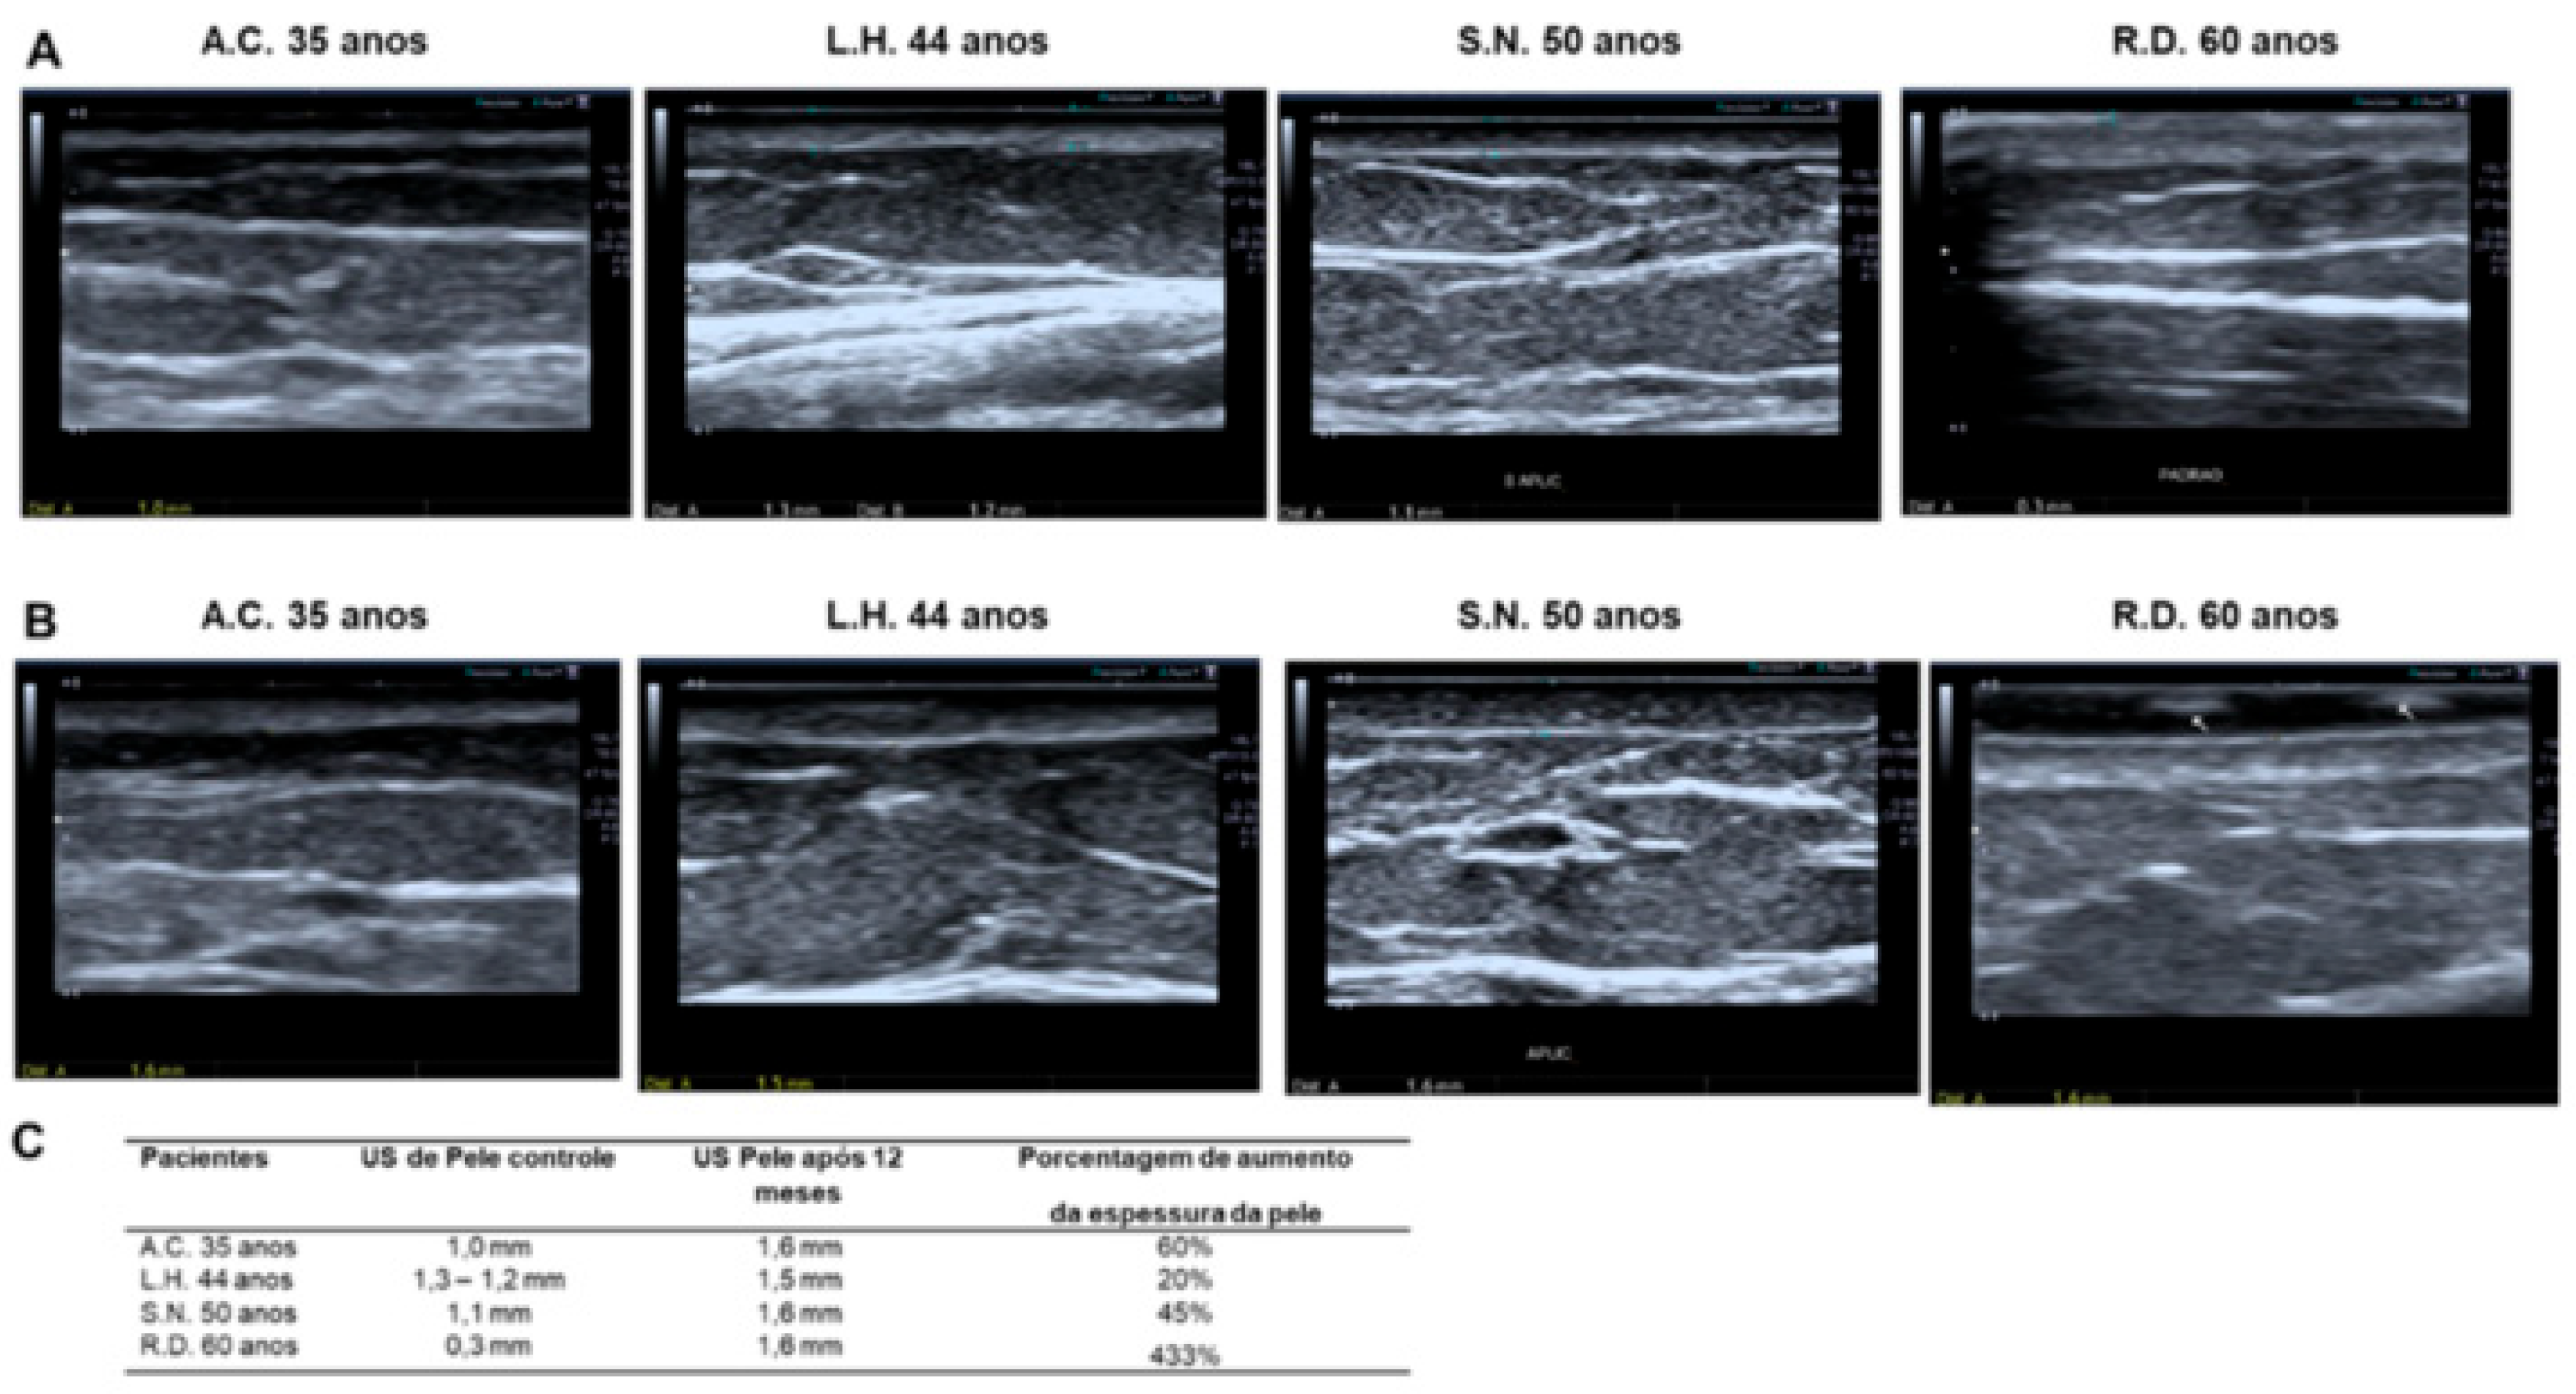

To elucidate the clinical improvement of the skin, as well as to confirm the increase in dermal thickness observed in the histological examination (Masson’s Trichrome staining), one year after the hyaluronic acid injection, the patients underwent an imaging exam, in which a cutaneous ultrasound was performed on each patient in the area subjected to the hyaluronic acid injection, as well as on the skin region not subjected to treatment and immediately next to the injection region. The same radiologist performed the ultrasound in all four cases studied. The data obtained by the skin ultrasound exam prove an increase in the thickness of the epidermis/dermis layer in all patients one year after the hyaluronic acid injection, which contributes to clinically proving the effective result of such treatment (Figure 10).

The ultrasound examination of the skin 12 months after the application of hyaluronic acid corroborates the macroscopic data regarding the thickening of the treated area, as observed through microscopic analysis using Masson’s trichrome staining in all patients in the study. This reinforces the permanence of the positive effect one year after the injection of hyaluronic acid.

Figure 10. Skin ultrasound. (A). Image of an untreated control area adjacent to the studied region, with measurements of the dermis-epidermis of the 4 patients according to their ages. (B). Image of the quadrant in which HA was applied, with measurements of the dermis and epidermis of the 4 patients according to their ages. (C). Table demonstrating the increase in dermis-epidermis thickness in the treated region after 12 months of the study, with the respective percentage of increase for each patient, compared with the adjacent region (control).